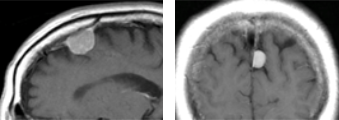

円蓋部髄膜腫

脳の表面を覆う硬膜から発生するタイプで最も頻度の高い腫瘍です。相当な大きさにならないと症状をきたしにくいことが多いので、MRI検査で偶然に発見されることが多いです。

この症例は、当初軽度の頭痛を主訴にMRIを行なったところ左前頭葉に2cmほどの腫瘍が偶然発見されました(左)。ほとんど症状が無く、日常生活に支障がなかったため、1年に1度検査を行い、経過観察していましたが、3年後に4cmとなりました(右)。それでも頭痛は軽かったのですが、腫瘍のサイズが少しずつ大きくなってきたため本人も不安となり、相談の上、開頭手術を行なった症例です。

このように脳の表面にできた場合は、いきなり手術を決断しなくても、治療を受けるか否か検討する猶予はありますので、よく考えたほうが良いです。